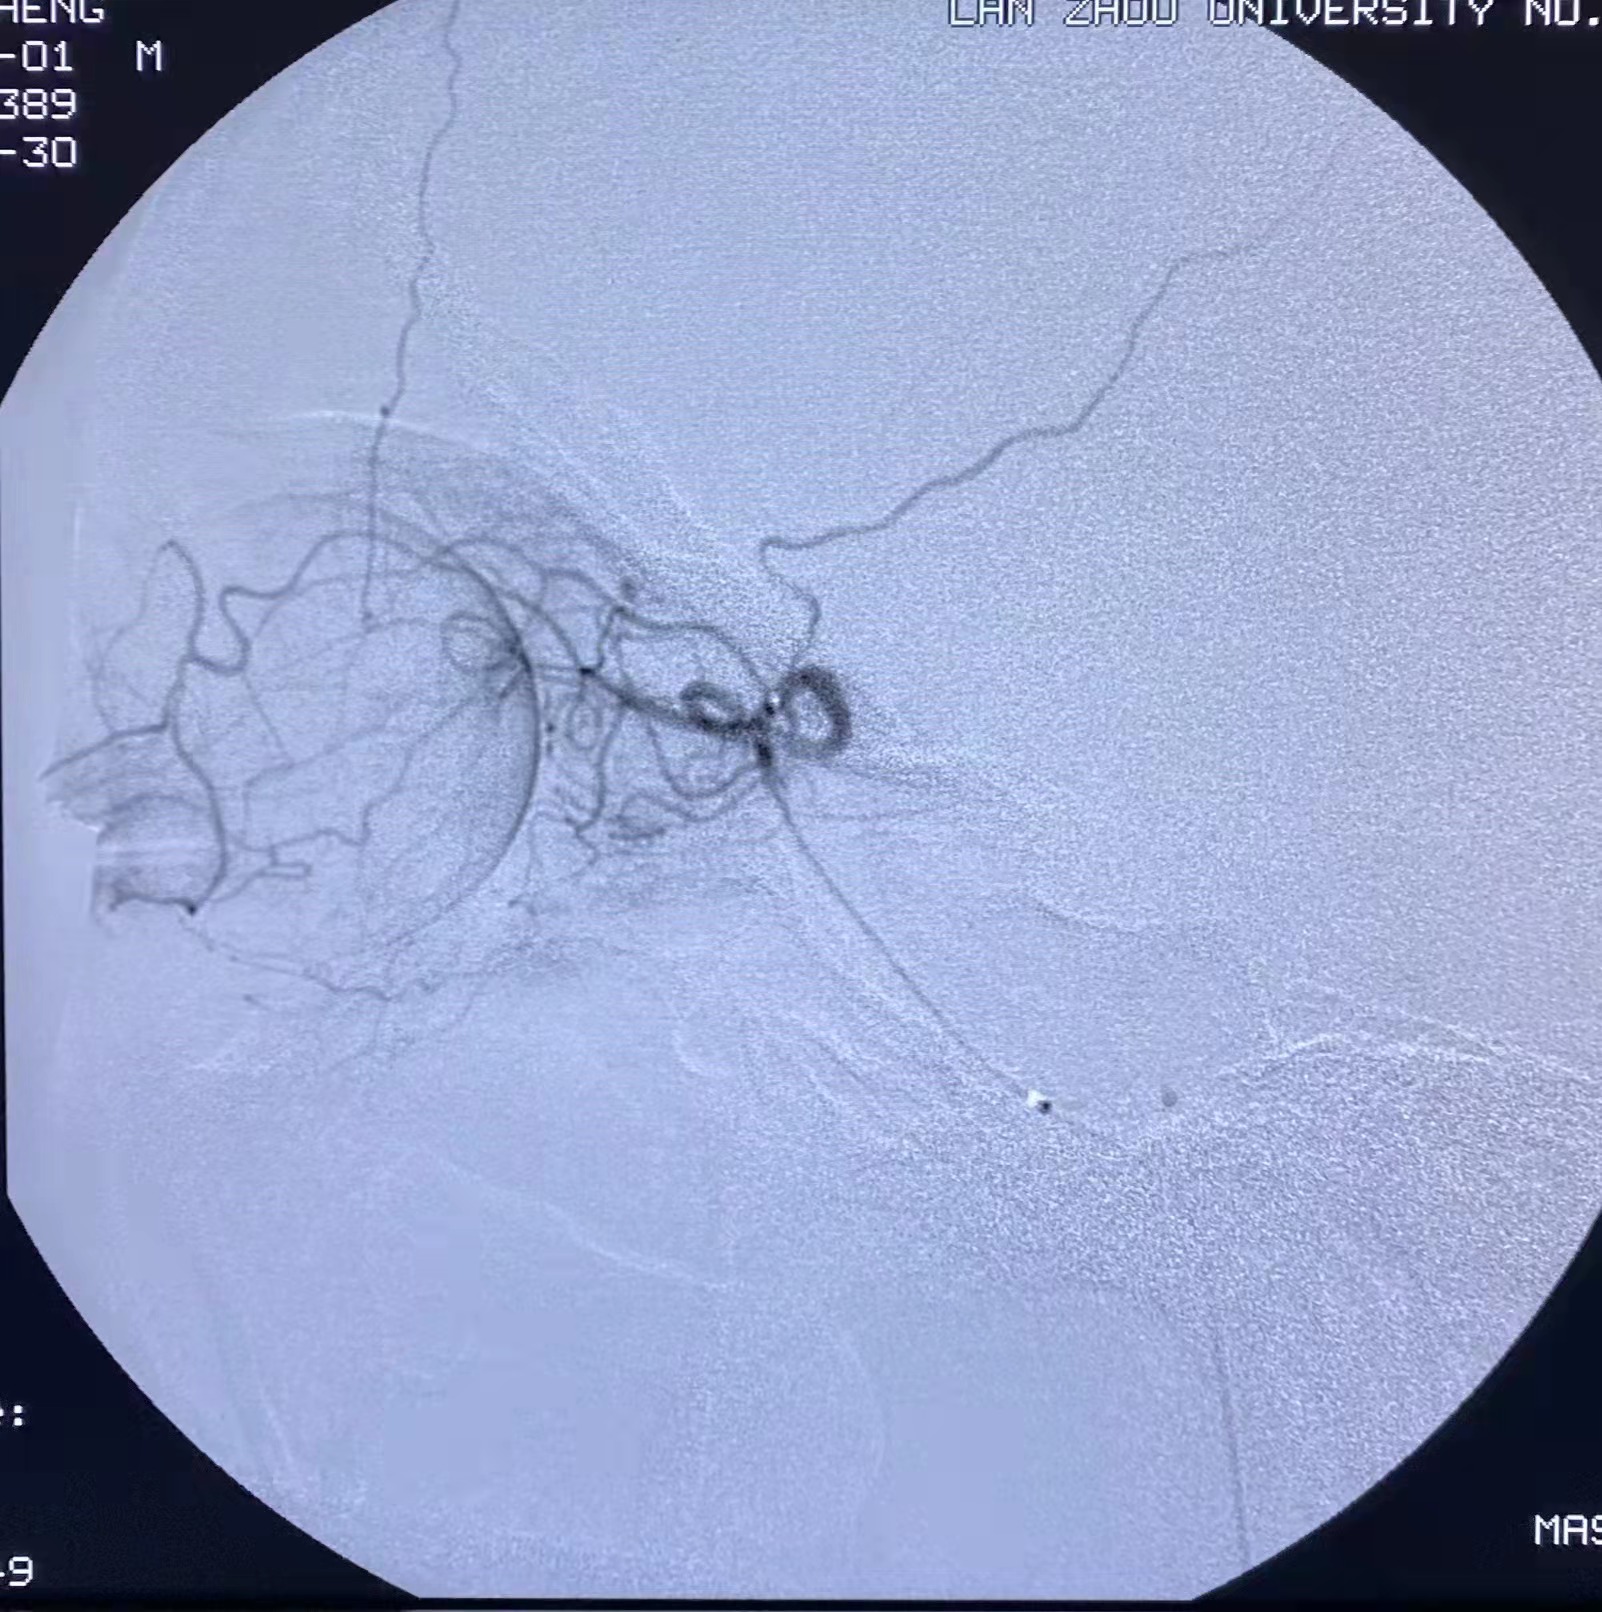

术前

术后

据悉,家住兰州市榆中县的27岁青年吴某突发右眼视物不见,右眼视力仅有光感,即就诊于兰大二院眼科。入院后,立即予以吸氧、扩血管、降眼压等常规治疗,但患者视力仍未见恢复,眼底荧光造影显示视网膜动脉闭塞,经常规保守治疗后患者症状未见好转,此时患者面临单眼失明。考虑患者比较年轻,在取得患者及家属同意后,主管医师立刻联系神经内科开通绿色通道,在神经内科三病区主任张振昶的指导下,王浩玥医生急诊实施了经导管超选眼动脉及泪腺动脉尿激酶溶栓治疗,并规律进行高压氧、改善循环等进一步治疗。术后血管造影显示眼动脉循环供血恢复,眼电生理各指标,提示较术前好转,患者视力较前有所恢复。随后,经副院长张文芳会诊,认为患者治疗有效,视力有望进一步提升。

术后视网膜造影剂淡然情况改善